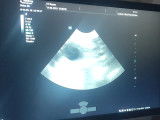

Des chiots Berger Malinois vont naître +- 2 avril 2026.

La mère est Opium de la Bouhaye(Sally de la Bouhaye x Nardo du feu de Wotan). C'est une femelle très stable, sociable, joueuse et vive.

Le père est Quartz of Joli Troucheaus(Lucky OJT x Nessa OJT)

Petit fils de Haras van d'Acren.

C'est un chien de patrouille police, il est très stable et sociable,

Les parents sont testés hanches/coudes/épaules par radios et Opium est testée par Adn pour les maladies génétiques du berger Belge.